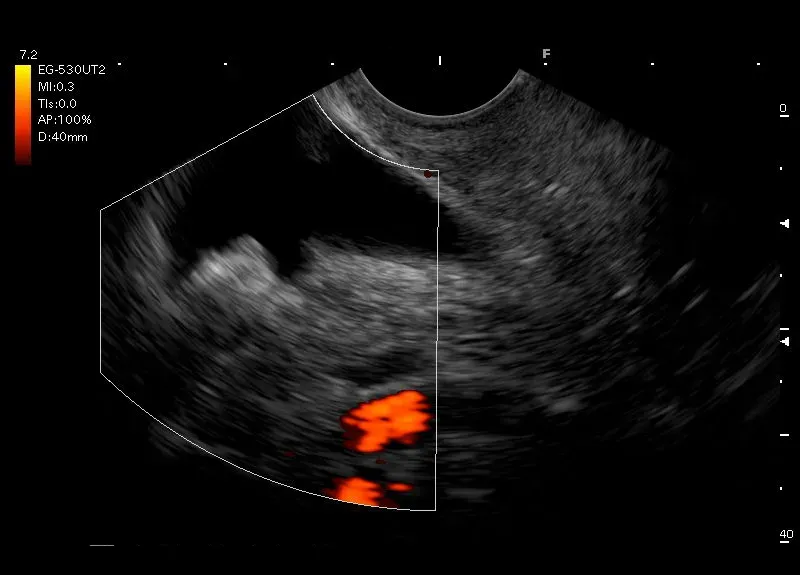

Pogrubienie ściany pęcherzyka żółciowego zawierające w ścianie torbiele, złogi cholesterolowe lub niewielkie przestrzenie bezechowe - adenomiomatoza pęcherzyka żółciowego

Pogrubienie ściany pęcherzyka żółciowego zawierające w ścianie torbiele, złogi cholesterolowe lub niewielkie przestrzenie bezechowe - adenomiomatoza pęcherzyka żółciowego